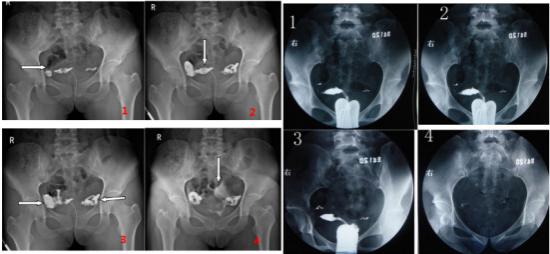

单某某、女、35岁,计划生育二胎未果,到医院检查,使用动态DR做子宫输卵管造影检查。检查过程中采用矩形数字化透视成像(43cm×43cm),观察造影剂流动情况,并对特征影像进行实时高清点片,获取900万像素影像如下:

图1、2清晰显示:左箭头示右侧输卵管迂曲,间质部、峡部通畅,显影良好;上箭头示子宫壁毛糙。图3、4可知:左、右箭头分别示右侧、左侧输卵管壶腹部和伞部积水扩张,右侧输卵管伞端部分造影剂流出,提示通而不畅;左侧输卵管未见明显造影剂流出,提示堵塞不通。上箭头示弥散至盆腔内的造影剂。综上所述,可以精准判定左侧输卵管堵塞。

动态DR影像与胃肠机影像对比

众所周知,在妇科检查中,胃肠机成像视野小,需要移动球管、探测器和床板,调整好位置,才能完整显示整个盆腔,曝光时间长,明显增加受检者X线吸收量;透视影像较为模糊,图像采集延迟,病灶部位的显示不容易捕捉。另外,胃肠机点片方面,目前有两种方式,一种是抽帧,其最大的缺点是获得的影像模糊,容易漏诊误诊;另一种方式是采用跑片机辅助成像,该过程时间较长,无法实时采集。另一方面动态DR矩形采集面积大,一次曝光即可显示整个盆腔,大幅减少观察时间,可控的瞬时照射避免受检者吸收过多的X线,对育龄期妇女、儿童的检查尤为重要。实时高清点片,可以在造影剂流动的过程中完成拍片,同时在在幼儿不规范摆位中快速抓拍到关键高清图像,对检查及诊断有非常重要的价值。